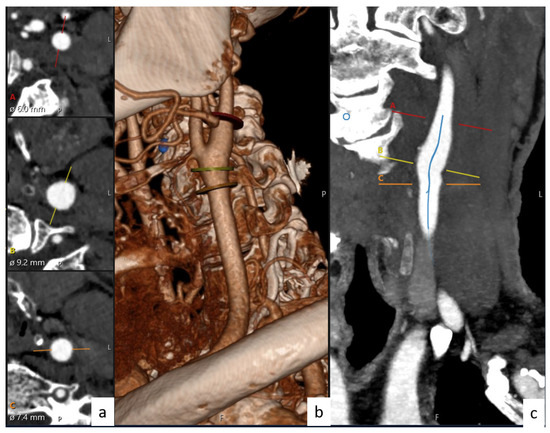

2.7. Data Collection

Figure 1. Illustration of the CCA, ICA, and ECA values and bifurcation angles of the vessels.

Figure 2. Diameters and angles of carotid artery with the help of Sectra software. (a) Diameter, (b) 3D imaging of carotid arteries, and (c) artery lumen centers.